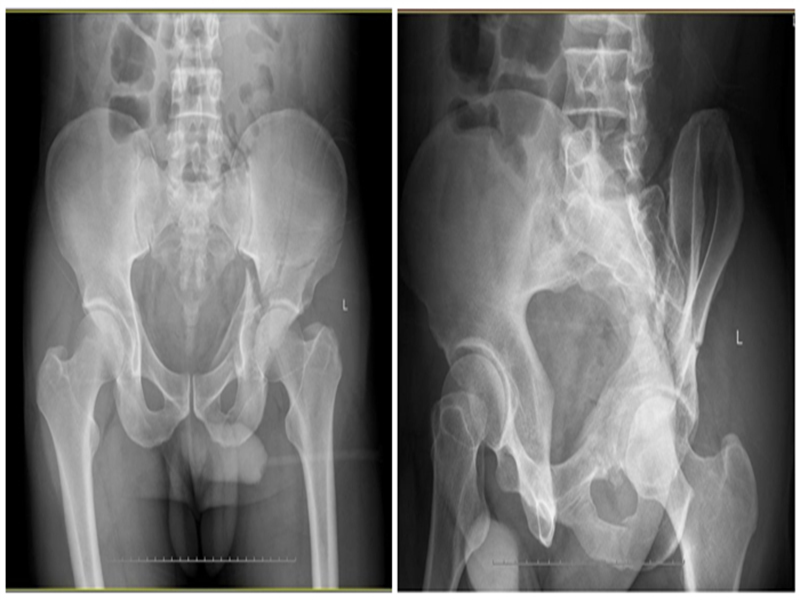

K-L K-L Stoppa